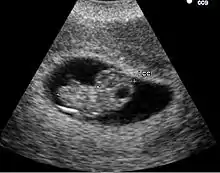

مررت العديد من الولايات ما بين سنتي 2011 و2012 تشريعات تنص على إلزامية خضوع المرأة الراغبة بالإجهاض بفحص عن طريق الأمواج الفوق صوتية.[39] شرعت بعض الولايات الطلب من المرأة عرض صورة الجنين في حين طلبت ولايات أخرى أن يقدم للمرأة فرصة الاستماع إلى نبض الجنين قبل عمليات الإجهاض. وبما أنه عمر الحمل لدى النساء الراغبات بالإجهاض قد يكون غير كافي للحصول على صورة بالأمواج الفوق صوتية للجنين بالطريقة التقليدية، شرعت بعض الولايات إجراء صورة بالأمواج فوق الصوتية عبر الإيلاج المهبلي. وقد جادل منتقدي هذا التشريع بعدم الضرورة الطبية لهذا الإجراء، إضافة إلى مشابهة لتعريف الاغتصاب وفق تشريعات بعض الولايات.[40] خضعت الكاتبة ميغان كاربنتييه لهذا الإجراء، وأشارت إلى أنه على الرغم عدم تشابه مع التعرض للاغتصاب، إلا أن هذا الفحص كان غير مريح، إضافة إلى الألم إضافة إلى أثاره العاطفية وهو الشيء ينبغي أن لا تجبر الحكومة مواطنيها على الخضوع له وجعل هذا الإجراء وجهة نظر سياسية.[41][42]